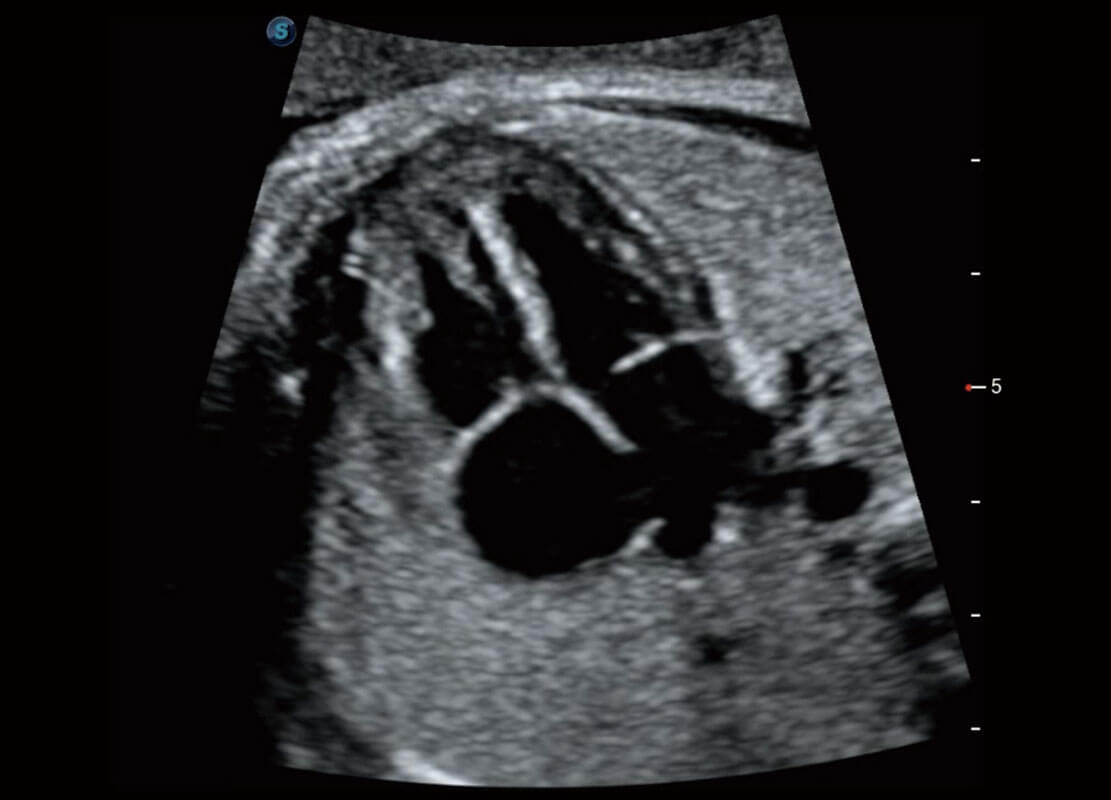

胎心筛查

P60搭载一系列胎儿心脏成像技术,实现精细的胎儿心脏评估。

• 四腔切面

• 四腔心血流

• 右室双出口

• 胎心容积成像